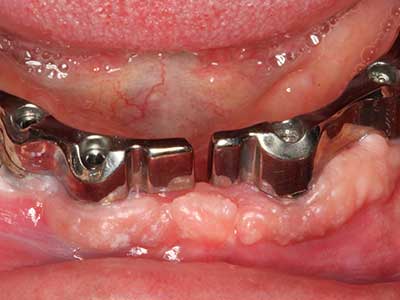

El tejido óseo no solo tiene un contenido puramente mineral, sino que también presenta una importante proporción de fibras de colágeno. Esto no solo garantiza una buena resistencia a la presión, sino también una cierta flexibilidad, que puede aprovecharse para la realización de aumentos. En la plastia de expansión clásica a efectos de una partición ósea, la cresta maxilar atrofiada se divide en su eje longitudinal y, tras alcanzar una profundidad de osteotomía suficiente, se extiende con cuidado (fig. 13-16), en un caso ideal sin desperiostizar de forma visible el maxilar (Brugnami, Caiazzo et al. 2014, Stricker, Fleiner et al. 2014). Los sistemas de tornillos y placas con distancia de expansión creciente han demostrado su eficacia para distanciar entre sí las dos tablas óseas por debajo del umbral de rotura. Por regla general, se requieren anchuras de hueso residual de al menos 3 a 4 mm (Chiapasco, Zaniboni et al. 2006) para garantizar una flexibilidad y una cobertura ósea suficientes de los implantes que van a incorporarse. En caso necesario, una osteotomía de descarga vertical unilateral o bilateral puede mejorar la flexibilidad. Como alternativa a la técnica clásica se ha descrito una combinación con otras técnicas de aumento, sobre todo en la parte bucal.

Con el uso de sierras piezoeléctricas la división se efectúa de forma especialmente cuidadosa y sin pérdidas importantes de las dimensiones, por lo que no se han encontrado diferencias significativas entre los implantes realizados en el maxilar dividido y en la cresta alveolar no deficitaria (Chiapasco, Zaniboni et al. 2006, Danza, Guidi et al. 2009). No obstante, precisamente en la partición profunda y limitada de forma local, es preciso asegurarse de que exista una adecuada irrigación por agua para evitar que se produzcan sobrecargas térmicas en las áreas de osteotomía apical.